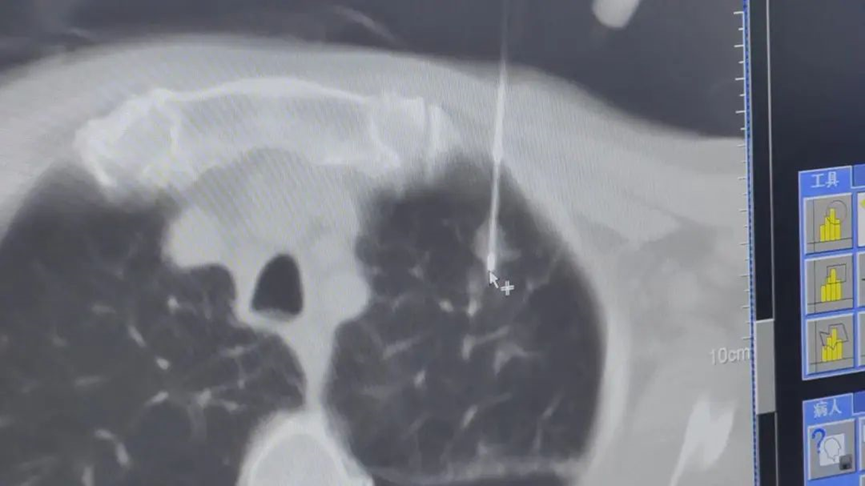

รายงานภาพก่อนผ่าตัด: ตุ่มเนื้อตั้งอยู่ในกลีบปอดซ้ายส่วนบน ใกล้กระดูกซี่โครงและเยื่อหุ้มปอด

ระหว่างขั้นตอนการรักษา

▲ เข็มความเย็น (Cryoablation) อันแรกถูกสอดเข้าไป โดยตุ่มเนื้อในปอดถูกกดลงอย่างนุ่มนวลเพื่อหลีกเลี่ยงการบาดเจ็บต่อเยื่อหุ้มปอดระหว่างการจี้เย็น

▲ เข็มอันที่สองถูกสอดตามมาและปรับมุมให้เหมาะสม จากนั้นทั้งสองเข็มถูกจัดให้อยู่ในตำแหน่งที่ลักษณะคล้าย "ตะเกียบ" เพื่อจับตุ่มเนื้อในปอดสำหรับการรักษา

▲ การสแกน CT แสดงให้เห็น "ก้อนน้ำแข็ง" ขนาด 4×3.3 ซม. ปกคลุมบริเวณปมอย่างสมบูรณ์ ในขณะที่ยังรักษาระยะห่าง 2 ซม. จากเยื่อหุ้มปอด เพื่อหลีกเลี่ยงอาการปวด